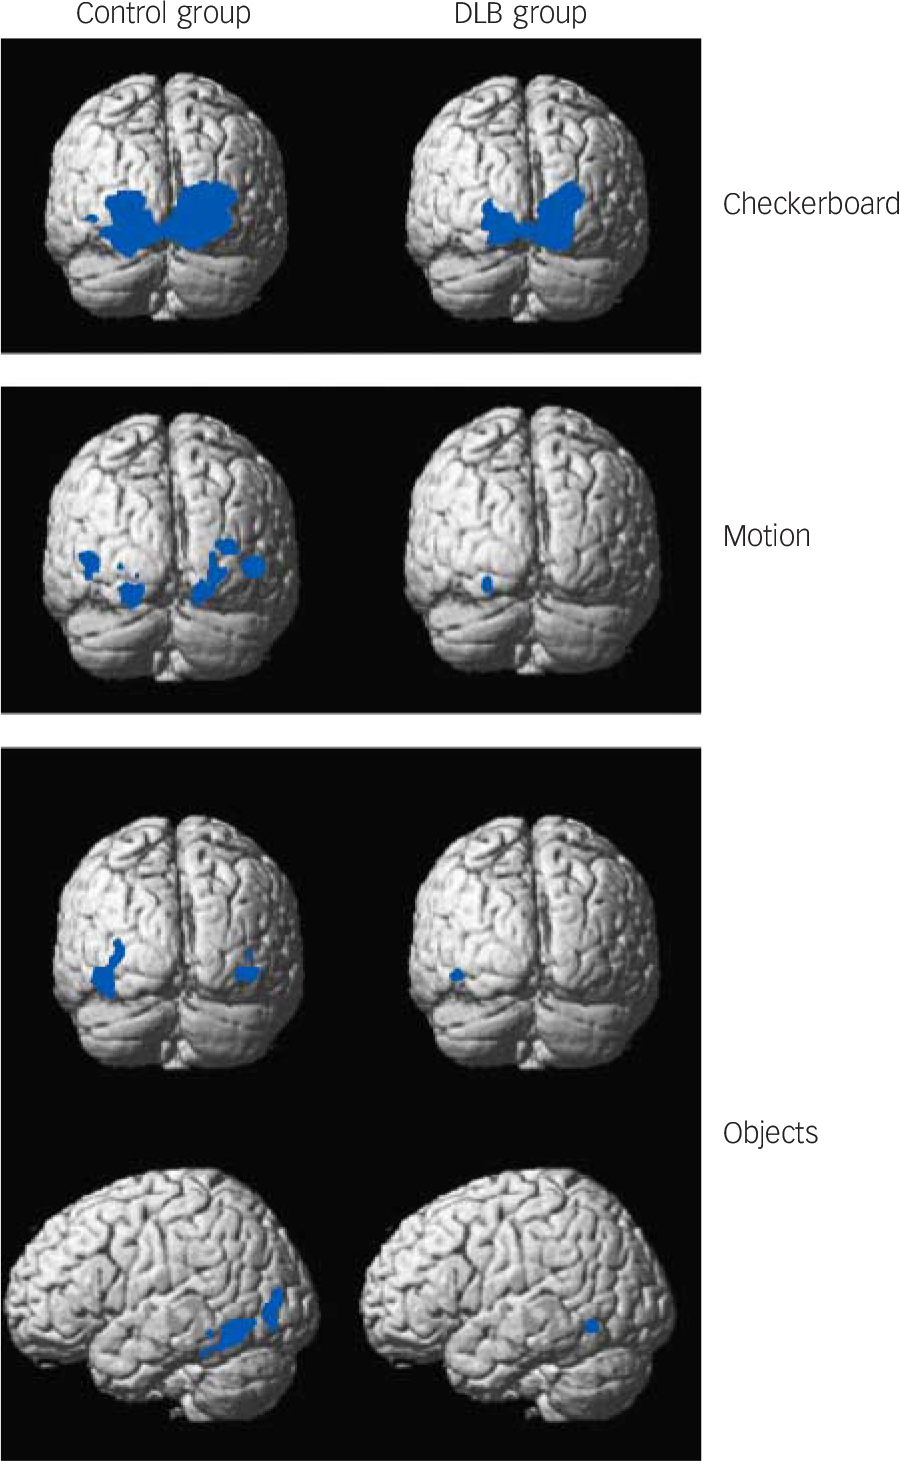

Fig. 1 Group activation maps for checkerboard, motion and objects stimuli. Blue areas indicate significant BOLD activation. See online Fig. DS2 for graduated colour activation maps.

Thresholded at P<0.05 family wise error corrected and superimposed on average brain template. Contrasts include checkerboard v. static image (checkerboard stimulus), moving dots v. static image (motion stimulus) and objects v. scrambled image (objects stimulus). BOLD, blood oxygen-level dependent; DLB, dementia with Lewy bodies.

Functional MRI activations

Distinct and overlapping networks (P<0.05 family wise error corrected) were evident for each of the visual stimuli for both control and DLB groups (Fig. 1 and Tables 2, 3, 4 and online Fig. DS2). Significant cluster activations for checkerboard stimulus lay within V1 and V2 for both control and DLB groups, with controls in addition showing significant clusters over V3. For the motion stimulus contrast, both DLB and control groups had significant activations in V3 and V4, with activation in V5/MT only present in the control group. The objects stimulus contrast demonstrated activation clusters in controls overlying the left inferior temporal gyrus, left fusiform gyrus, left inferior and middle occipital gyrus. No clusters ≥20 voxels were noted in participants with dementia with this stimulus.

Whole brain analyses comparing groups, however, did not demonstrate any significant differences in activation between DLB and control groups for each of the tasks. Region of interest analysis (Fig. 2) for lower visual areas confirmed this finding, with no differences in activity between the control and DLB groups for checkerboard stimulus (V1 ROI) or objects stimulus analyses (LOC ROI). However, the ROI localised on the V5/MT showed that the DLB group had reduced activation to the motion stimulus in this area compared with controls (P = 0.02). The results of the exploratory analyses of BOLD activity in the other ROIs for each of the tasks are shown in online Table DS1. Of note, there were no significant differences between DLB and control groups in the BOLD response to the three visual stimuli in V1, V2/3 or V4.